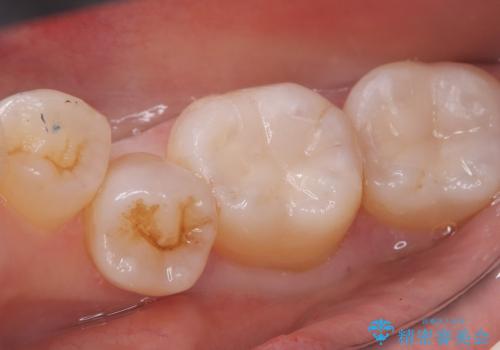

下顎大臼歯部に入っている保険適用のメタルインレーを、適合性と審美性の良いセラミックインレーでのやり替えとなりました。

メタルインレーを除去した際、古い裏層材やカリエスは除去し新たにCR裏層しています。

セラミックインレーセット時はラバーダム防湿を行っています。